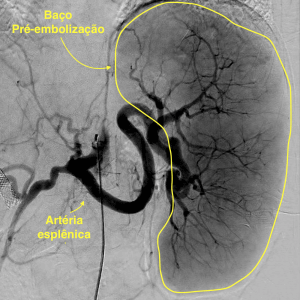

A Embolização esplênica é realizada durante um procedimento de arteriografia, também conhecido como “cateterismo”. Trata-se de um procedimento moderno, com utilização de recursos tecnológicos que permitem que a técnica seja realizada com apenas um pequeno furinho na virilha ou no punho, utilizando-se na grande maioria das vezes apenas anestesia local ou uma leve sedação.

Um pequeno cateter é introduzido por meio desse furinho, de forma indolor, e a partir desse cateter um outro cateter milimétrico é posicionado no interior das artérias do baço. Nos locais almejados, o médico Radiologista Intervencionista realiza a injeção de materiais sintéticos (ex: microesferas de gelatina) até ocasionar a interrupção do fluxo sanguíneo para uma parte do órgão. Como consequência, haverá uma redução controlada do tamanho do órgão e de sua funcionalidade, permitindo que aumente o número de plaquetas. Ao final do procedimento retiram-se os cateteres e é feito um curativo no local do furinho. Os pacientes submetidos à embolização costumam ficar internados em média por 12-24 horas no hospital.